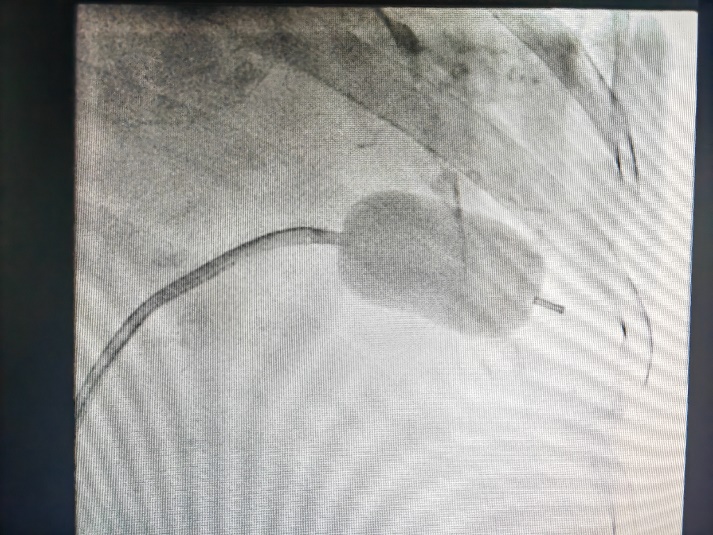

图四:球囊对狭窄的二尖瓣进行扩张

此例手术由姚晓伟主任医师、韩稳琦主治医师、赵永勇主治医师通过心腔内超声指导下进行,通过心腔内超声精准构建心脏模型、直视下穿刺房间隔,后通过心腔内超声及左心房造影寻找狭窄的二尖瓣瓣口,并指引二尖瓣球囊扩张导管顺利经狭窄的二尖瓣口至左心室,在心腔内超声的指引下选择最佳位置以26mm球囊导管反复扩张狭窄的二尖瓣。术后第二天复查心脏超声,患者二尖瓣瓣口面积由术前0.67cm2扩大到术后1.69cm2,二尖瓣跨瓣压差由术前22mmHg降低至术后的16mmHg,左房前后径由术前94mm减小至术后92mm,左房左右径由术前109mm减小至术后102mm,并且球囊扩张后未引起明显的二尖瓣反流,患者心功能明显改善,自觉症状明显好转出院。

经皮二尖瓣球囊扩张成形术因其不需要开胸、创伤小、术后恢复快、严重并发症少见、作用明显而被广泛应用于临床治疗二尖瓣狭窄。心血管内二科独立成功完成此例罕见、复杂、高风险二尖瓣狭窄患者心腔内超声指引下的经皮二尖瓣球囊扩张成形术,标志着五楼自拍